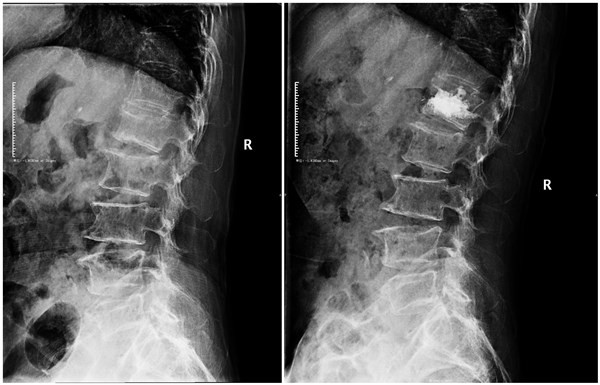

腰1椎体压缩性骨折术前术后正位片

腰1椎体压缩性骨折术前术后侧位片